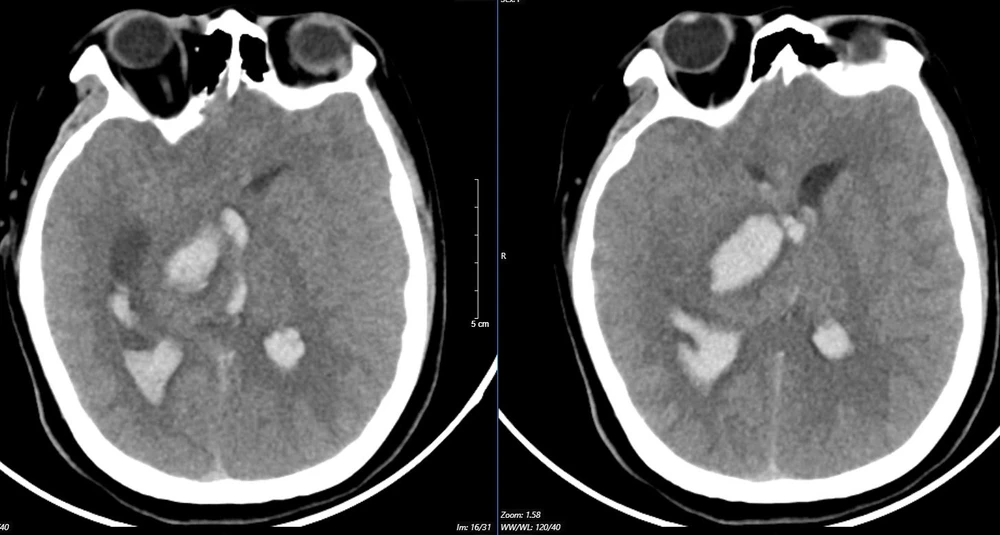

Kết quả chụp cắt lớp điện toán đa lát cắt (MSCT) mạch não cho thấy bệnh nhân bị chảy máu não đồi thị - não thất do vỡ khối AVM (dị dạng thông động - tĩnh mạch não), biến chứng giãn não thất cấp, rối loạn thân nhiệt, sốt cao liên tục 39 - 40 độ C.

Hình ảnh chụp MSCT mạch não cho thấy bệnh nhân 15 tuổi bị chảy máu não đồi thị - não thất do vỡ khối AVM. Ảnh: BVCC